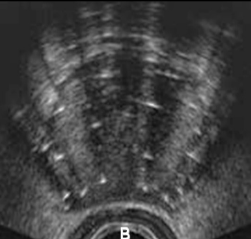

Identify this image.

Peripheral zone

Central and transitional zone

Urethra